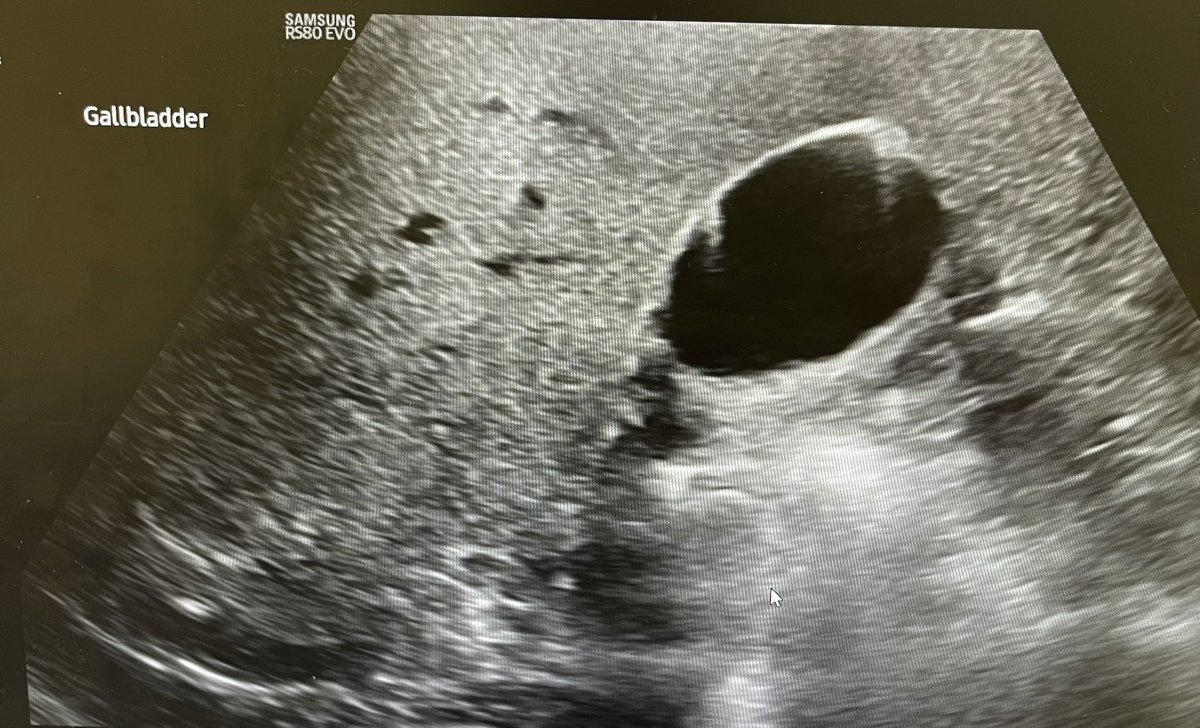

Gall stone. GB adenomyomatosis, Hepatic steatosis. @Rad_Munagi